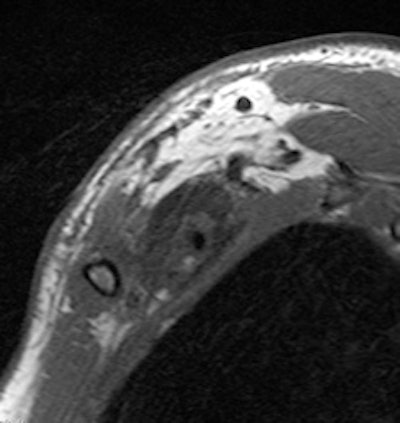

Young man who underwent a brachial plexus MRI examination following a motorcycle accident. A complex brachial plexus lesion is depicted. This case has been considered a true positive. All images courtesy of Dr. Alberto Tagliafico.

Patients ranged in age from 18 to 84 years. Their lesions detected by MRI represented a mix, including 35 root avulsions and brachial plexus cord injuries, 22 primary or secondary tumors, and four each entrapment syndromes, fibrous scars, and Parsonage-Turner syndrome.